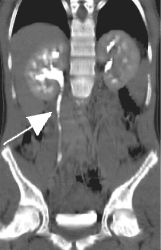

Right image is a curved coronal reconstruction urogram clearly showing partial obstruction with a dilated right ureter and collecting system (arrow) proximal to the stone.

This is performed on an Advanced 4D Silicon Graphics Workstation to produce "IVP-like" coronal sections depicting the course of the ureters as shown in the top right image.